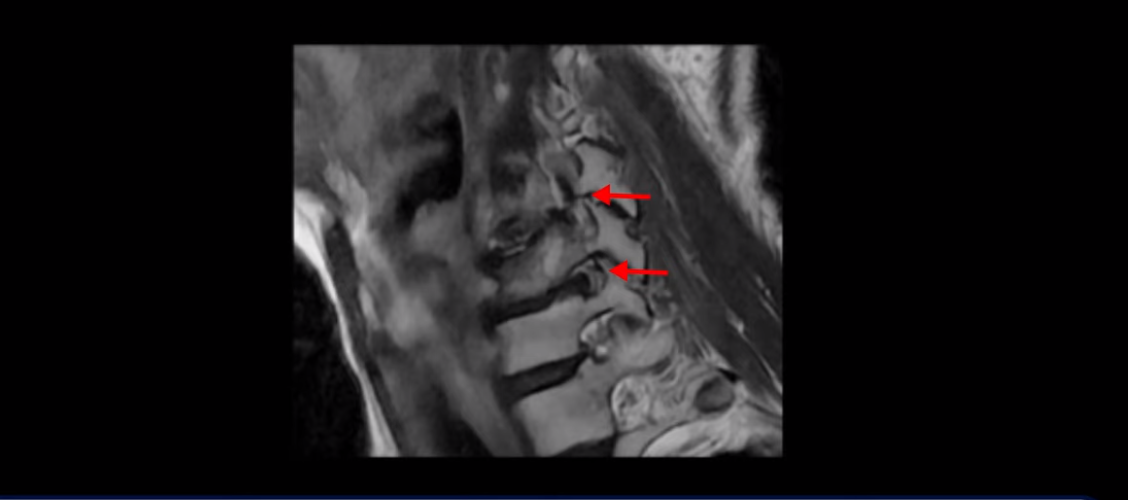

먼저 이분 MRI와 X-ray 보면서 간단히 설명해 드린 후 어떻게 목 협착증으로 신경이 눌려서 극심한 목통증과 견갑골 통증이 몇 달씩 지속되고, 고개가 조금도 돌아가지 않고 하루 24시간 아파서 잠도 잘 수 없는 환자가 수술 없이 비수술 치료로 좋아질 수 있는지, 치료는 어떻게 하는지 자세히 설명해 드리겠습니다. 참고로 이 환자분의 치료 후기는 2개입니다. 이분은 허리에도 심한 전방전위와 협착이 있어서 목 치료와 함께 허리 치료도 받으셨고, 허리 치료 후기 영상도 있으니 별도로 보시길 바랍니다.

이분 목 X-ray를 보면 역C자형의 목에 전방전위도 보이고,

두 마디의 디스크가 거의 닳아서 뼈들이 거의 붙어 보입니다.

목도 많이 휘어 보입니다.

MRI를 보면 2마디 디스크의 퇴행이 아주 심해 보입니다.

그래서 오른쪽 신경 가지가 빠져 나가는 추간공 2개와

왼쪽 추간공 두 개가 모두 많이 좁아져 있습니다.

이렇게 신경 구멍들이 좁아져 있고 신경 주사가 효과가 없으니까 동네 정형외과에서는 무조건 대학병원으로 가라고 했는데요. 가서 수술 받으라는 얘기겠죠. 그런데 저희 모커리한방병원은 협착증은 수술 없이 치료가 잘 될 수 있는 질환이라고 계속 설명하고 있는데요. 왜 그럴까요? 저희가 협착증이 왜 수술 없이 치료 가능하다고 설명하는지에 대해 잘 이해하시려면 무증상 협착이라는 개념에 대해 잘 이해하셔야 합니다.